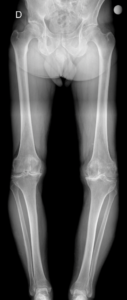

São deformidades do joelho no plano coronal, aquelas observadas de frente.

- Joelho varo (genu varum): pernas arqueadas, cambotas

- Joelho valgo (genu valgum): joelhos em X

Essas alterações modificam a forma como o peso do corpo é distribuído sobre o joelho. Ou seja, um joelho com deformidade, não distribui a carga uniformemente causando a sobrecarga da cartilagem articular em algum compartimento. Assim, no joelho varo, há uma sobrecarga no compartimento medial (interno) e no joelho valgo, no compartimento lateral (externo).

7. Como é feito o diagnóstico?

O diagnóstico é realizado por meio de:

- Avaliação clínica

- Análise do alinhamento dos membros

- Radiografia panorâmica em carga

Esses exames permitem identificar o grau da deformidade e indicar o melhor tratamento.